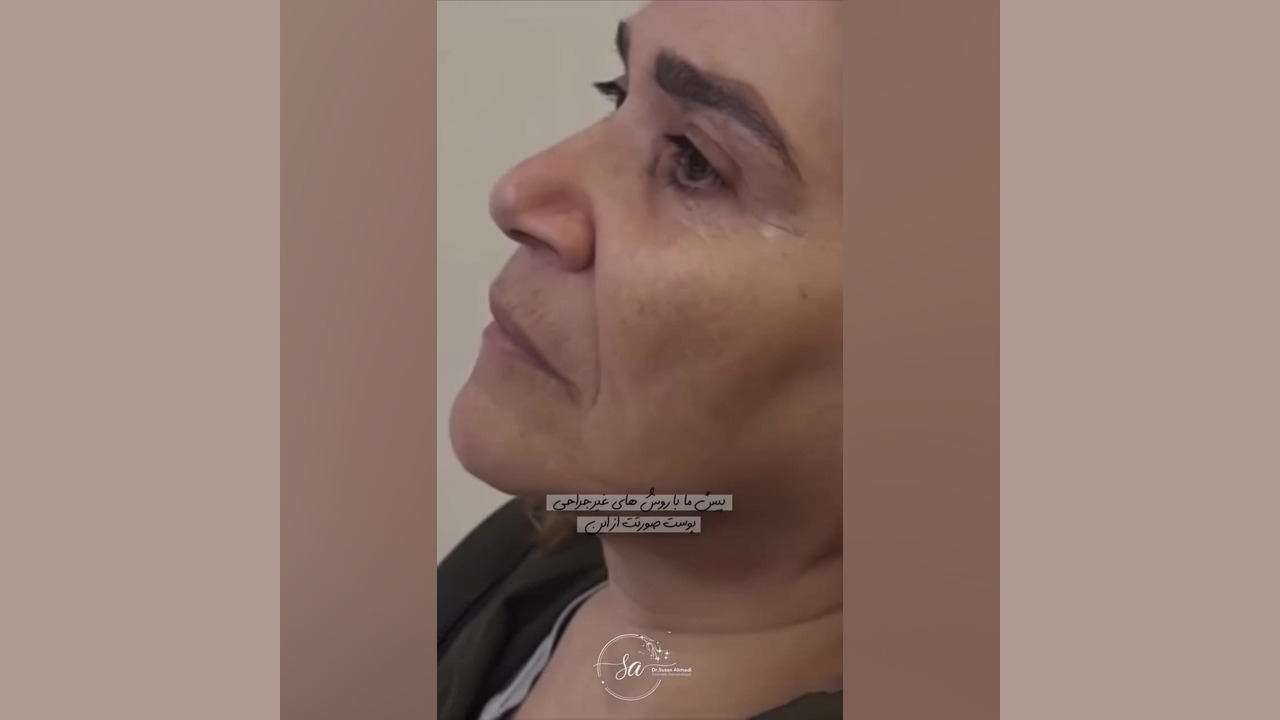

سیاهی و گودی زیر چشم مشکلی رایج است که میتواند بر زیبایی و اعتماد به نفس افراد تاثیر منفی بگذارد. خبر خوب این است که روشهای درمانی مختلفی برای رفع این مشکل وجود دارد. در این مقاله، به بررسی تزریق زیر چشم توسط دکتر احمدی، یکی از متخصصان برجسته در این زمینه، میپردازیم. با ما همراه باشید تا با این روش نوین، مزایا، عوارض ویدیوی تغییر شگفتانگیز آن آشنا شوید.

سیاهی و گودی زیر چشم عارضهای شایع است که به دلایل مختلفی از جمله ژنتیک، خستگی، کمآبی بدن، آلرژی و افزایش سن ایجاد میشود. این مشکل میتواند باعث شود افراد پیرتر و خستهتر به نظر برسند. خوشبختانه، روشهای مختلفی برای درمان سیاهی و گودی زیر چشم وجود دارد، از جمله استفاده از کرمهای مراقبتی، تغییر سبک زندگی و انجام روشهای درمانی پزشکی.

ویدیو تغییر شگفتانگیز: قبل و بعد از تزریق

برای مشاهده نتایج شگفتانگیز تزریق زیر چشم توسط دکتر احمدی، میتوانید ویدیوی قبل و بعد از تزریق را در [لینک ویدیو] مشاهده کنید. در این ویدیو، میتوانید تغییرات چشمگیر در ظاهر بیماران پس از انجام تزریق را مشاهده کنید.

دیدن این تغییرات میتواند به شما در تصمیمگیری بهتر کمک کند و انتظارات واقعبینانهای از نتایج این روش داشته باشید.